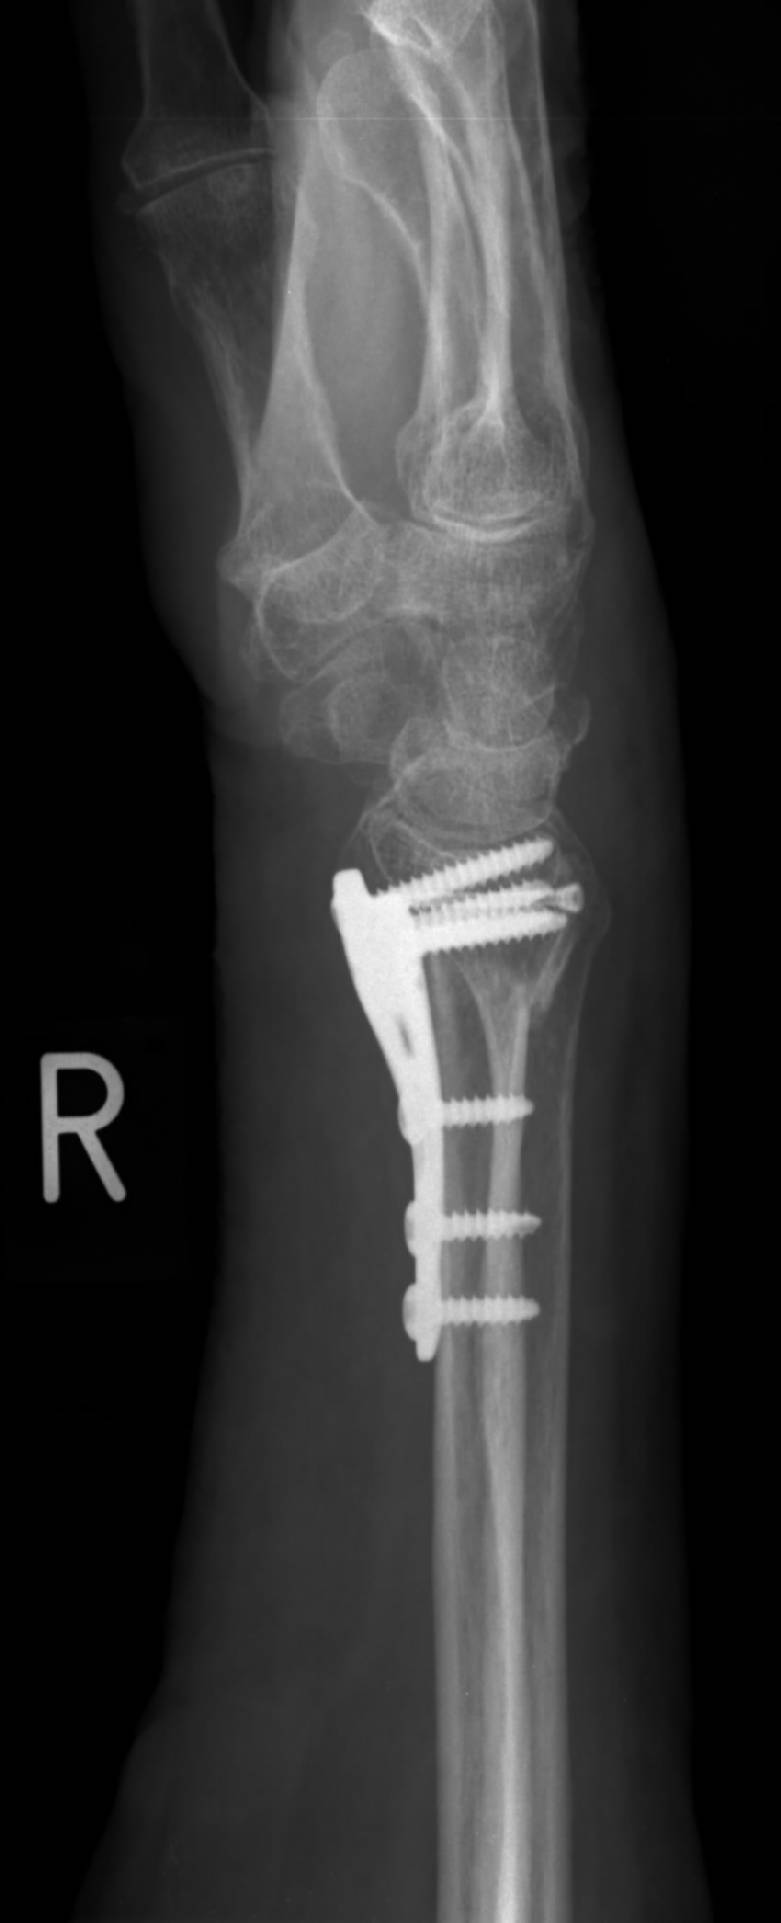

Eine Extremität oder ein Gelenk ist im Bereich der Fraktur ungewöhnlich beweglich. Behandlungen und Medizin /. Meist lassen sie innerhalb von sechs Wochen deutlich nach. Wirbelbrüche verursachen oft keine oder kaum Beschwerden, können aber auch manchmal zu starken Schmerzen führen.Wie ein Knochenbruch bei Kindern verheilt, zeigt auch folgendes Video: In der Regel erfolgt nach sieben bis zehn Tagen eine Röntgenkontrolle mit Gips, um die korrekte Stellung des Knochens zu gewährleisten. Winkelstabile Plattenosteosynthese / Biologische Osteosynthese.

Unterarmbruch

Distale Radiusfraktur: Behandlung & Spätfolgen